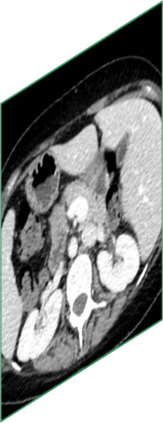

Due to the constraints of the imaging device and high cost in operation time, computer tomography (CT) scans are usually acquired with low intra-slice resolution. Improving the intra-slice resolution is beneficial to the disease diagnosis for both human experts and computer-aided systems. To this end, this paper builds a novel medical slice synthesis to increase the between-slice resolution. Considering that the ground-truth intermediate medical slices are always absent in clinical practice, we introduce the incremental cross-view mutual distillation strategy to accomplish this task in the self-supervised learning manner. Specifically, we model this problem from three different views: slice-wise interpolation from axial view and pixel-wise interpolation from coronal and sagittal views. Under this circumstance, the models learned from different views can distill valuable knowledge to guide the learning processes of each other. We can repeat this process to make the models synthesize intermediate slice data with increasing inter-slice resolution. To demonstrate the effectiveness of the proposed approach, we conduct comprehensive experiments on a large-scale CT dataset. Quantitative and qualitative comparison results show that our method outperforms state-of-the-art algorithms by clear margins.